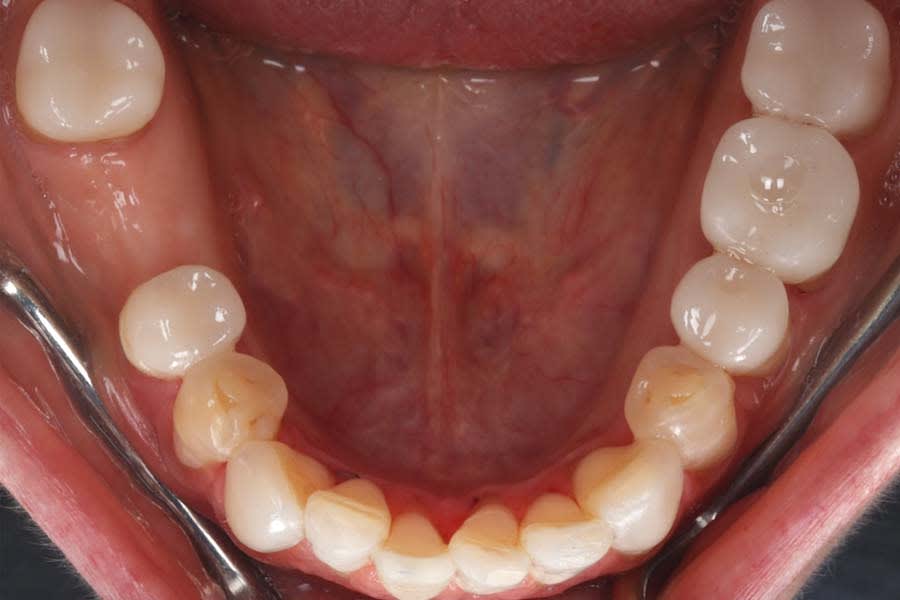

Definitive digital scans of each arch were obtained (Figure 7 and Figure 8), and the definitive restorations were designed based on the diagnostic wax-up (Figure 9). The design files were then exported in standard tessellation language (STL) format and transferred to the in-house technicians for milling of the definitive restorations in lithium-disilicate material. The restorations were subsequently custom-stained and glazed (Figure 10). Based on the patient’s esthetic preferences, modifications were made to the maxillary anterior design before delivery. The definitive restorations were evaluated intraorally and bonded with a luting composite (soft white shade) (Variolink® Esthetic LC, Ivoclar) (Figure 11), with all excess cement carefully removed (Figure 12 and Figure 13). The mandibular incisors were restored with direct composite, and abrasion lesions in the esthetic zone, intended for future root coverage, were provisionally restored with supragingival flowable composite for improved appearance (Figure 14).

The patient expressed satisfaction with the final esthetic outcome (Figure 15). An occlusal appliance was fabricated and delivered, and preventive strategies and maintenance protocols were reinforced with the patient. She was advised to maintain regular dental recall and topical fluoride varnish application. With compliance to these recommendations, a favorable long-term prognosis is anticipated.